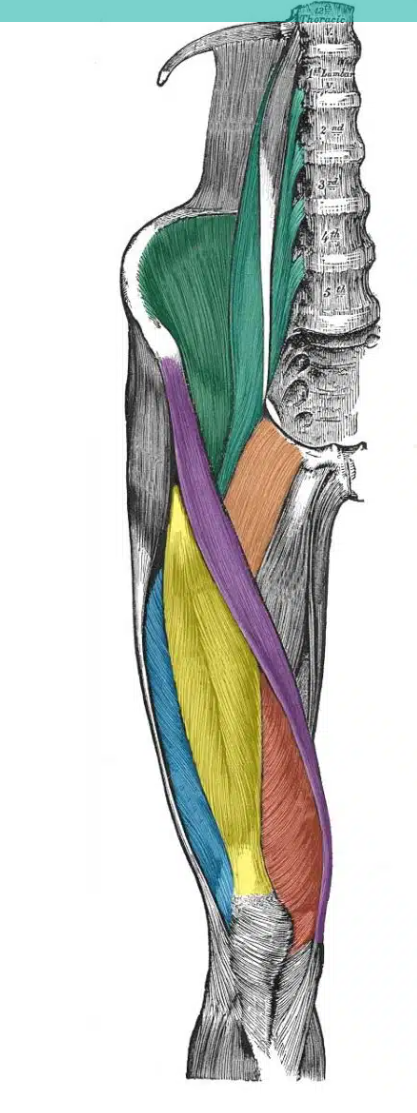

green vertical muscle- close to spine

A

psoas major

How well did you know this?

1

Not at all

2

3

4

11

Q

green muscle - in the iliac fossa

iliacus

5

Perfectly

12

yellow

rectus femoris

13

red

vastus medialis

14

blue

vastus lateralis

15

purple

sartorius